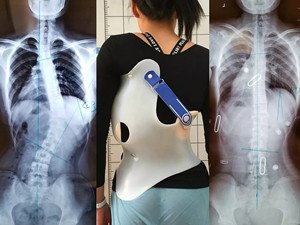

在青少年快速發(fā)育期內(nèi),身體長得越快,脊柱側(cè)彎的進(jìn)展就越快。矯形支具通過長時(shí)的反向矯正力將脊柱維持在一個(gè)矯正的狀態(tài);然而由于長時(shí)間地佩戴支具會(huì)導(dǎo)致肌肉萎縮,當(dāng)支具摘除,脊柱側(cè)彎回彈,且患者無法形成成自我矯正力,呼吸功能亦無法得到改善。最好是在穿戴支具的同時(shí),配合體操訓(xùn)練,通過一系列矯正動(dòng)作以及呼吸訓(xùn)練,平衡肌力,兩者結(jié)合不但可以穩(wěn)定脊柱,且能增加改善機(jī)會(huì)。